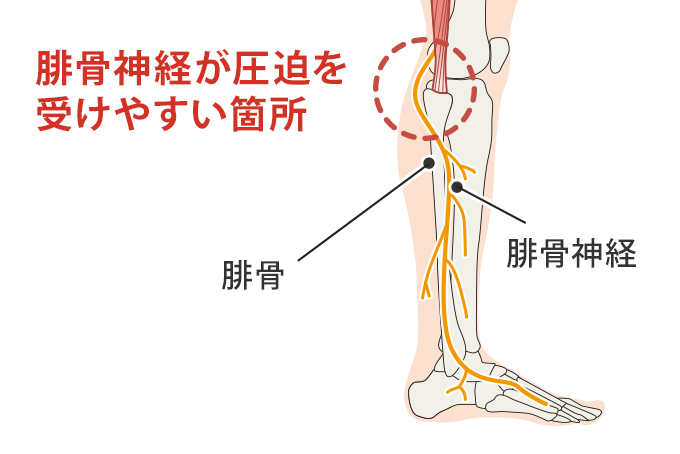

腓骨神経麻痺とは

坐骨神経から枝分かれした神経の一つ『総腓骨神経』。

これが何らかの原因で圧迫されてしまい、膝の外側から足の甲にかけてしびれが出てきたりします。

腓骨神経麻痺の原因

腓骨神経麻痺の最も多い原因としては、外部からの圧迫により生じるものです。

大腿骨骨折の際に行う下肢牽引・下腿外旋位(膝の外側がずっと下にある状態)。

身近なものでいうと足を組んで座っていたりする。

そうすると、腓骨頭が後ろから圧迫され神経も圧迫されてしまいます。